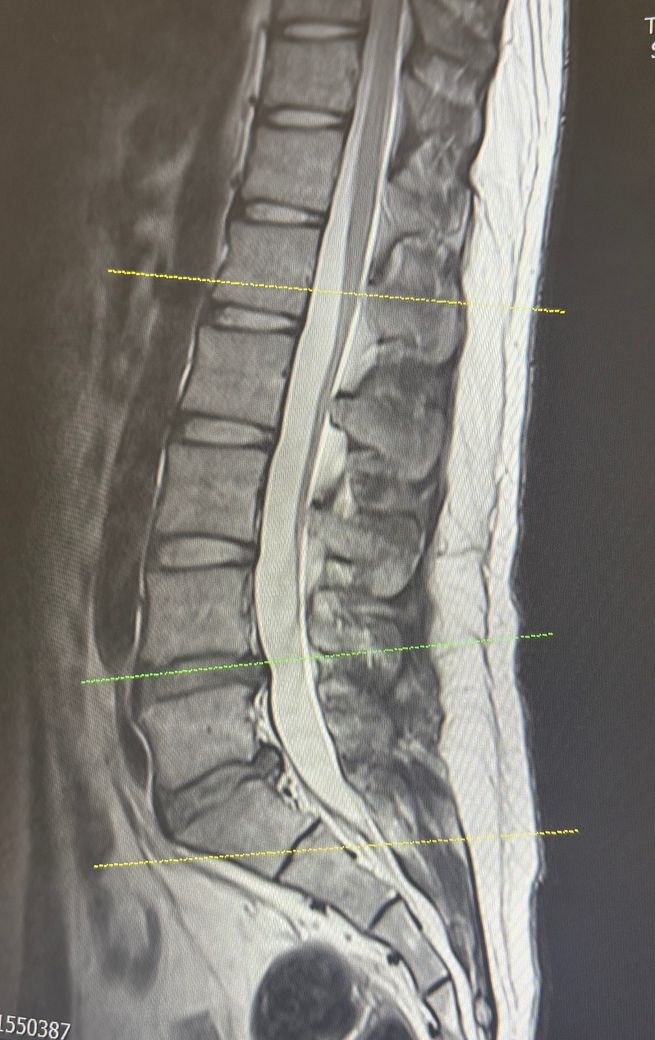

허리디스크 추간판 탈출증 좌측하지 방사통

군대 현부심 할려고하는데 가능할까요 왼쪽 허벅지 뒤 땡김이랑 발목이 잘 안올라가요 누워있으면 허리가 뜨거워지면서 쑤시고 많이 저려요.. 걷는것도 쩔뚝 거리면서 걸려요 허리쓰는 활동이 많아서 도 심해질까 걱정되네요..

디스크 진단만으로는 등급판정 시 4급이 나올 가능성은 적고, 올려주신 MRI나 신경증상 및 기능장애 여부들이 증요합니다.